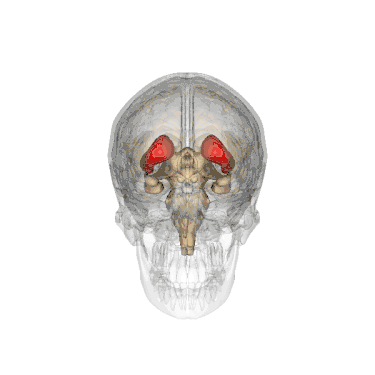

Смугасте тіло (лат. corpus striatum) - підкіркове утворення переднього мозку і надзвичайно важливий компонент екстрапірамідної системи й системи винагород (англ. Reward System), яке отримує глутамінергічні та дофамінергічні імпульси з різних структур і служить вхідними воротами імпульсів до решти системи базальних гангліїв. У всіх приматів волокнами білої речовини, які називають внутрішньою капсулою, дорзальна частина смугастого тіла ділиться на дві частини, які називаються хвостате ядро і сочевицеподібне ядро. Вентральна частина складається з прилеглого ядра і нюхового горбка. Смугасте тіло координує декілька когнітивних функцій, включаючи рухи й їхнє планування, прийняття рішень, мотивації, підкріплення й винагороду.

Смугасте тіло поділяється на дорзальну й вентральну частини відповідно до анатомічного розташування і функціональних зв'язків. Вентральний стріатум складається з прилеглого ядра і нюхового горбка, в 'дорсальний стріатум входять хвостате ядро і лушпина.

Анімоване зображення смугастого тіла

Смугасте тіло. Пряма й бокова проекції